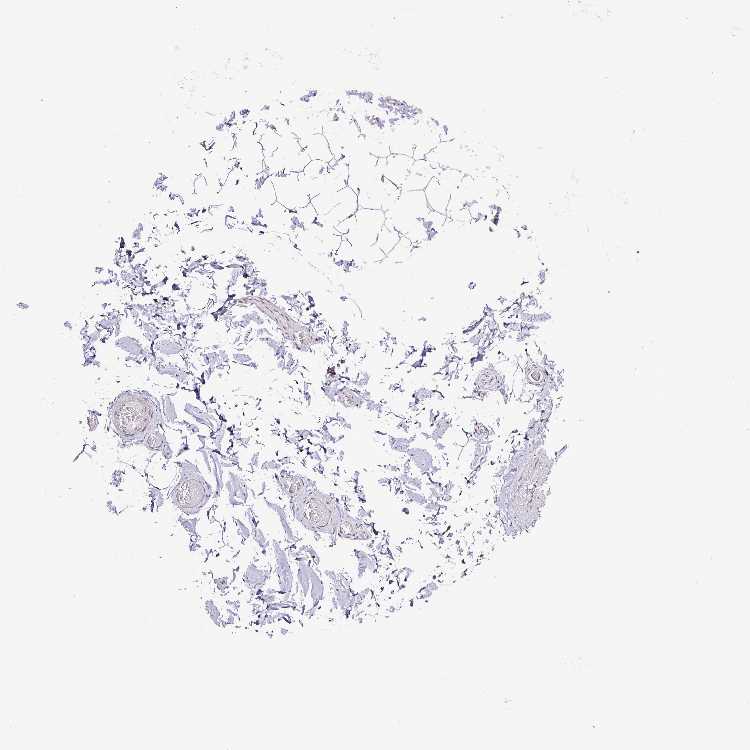

ADIPOSE TISSUE - Antibody stainingi

Antibody staining in the annotated cell types in the current human tissue is reported as not detected, low, medium, or high, based on conventional immunohistochemistry profiling in selected tissues. This score is based on the combination of the staining intensity and fraction of stained cells.

Each image is clickable and will lead to virtual microscopy that enables deeper exploration of all samples and also displays staining intensity scores, fraction scores and subcellular localization as well as patient and tissue information for each sample.

Antibody HPA041120

Adipocytes Medium